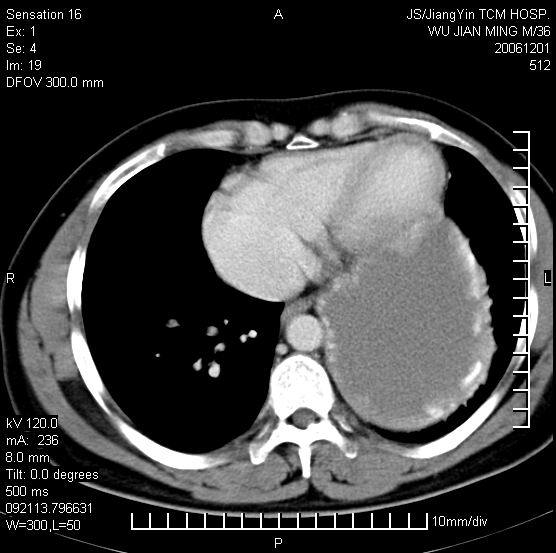

以下是引用dyqct在2006-12-1 21:17:00的发言:[br]左心缘旁及后肋膈窦区见巨大椭圆形混杂密度肿块,周围见大小不等斑片状钙化,内部无强化,周围包膜轻度强化,心脏明显受压变形,即明显占位效应,肿块广基与心包、膈相连。肝、脾内、肝门见多数小结节状钙化影。[br]考虑:1、左心缘旁及后肋膈窦区慢性包裹性胸膜炎(结核性);[br] 2、肝、脾及肝门淋巴结核已钙化。[br]

以下是引用zrs在2006-12-2 17:28:00的发言:[br]肺内、肝脾内虽有钙化,但不支持结核性胸胸膜炎包裹,而支持寄生虫感染![br][br]